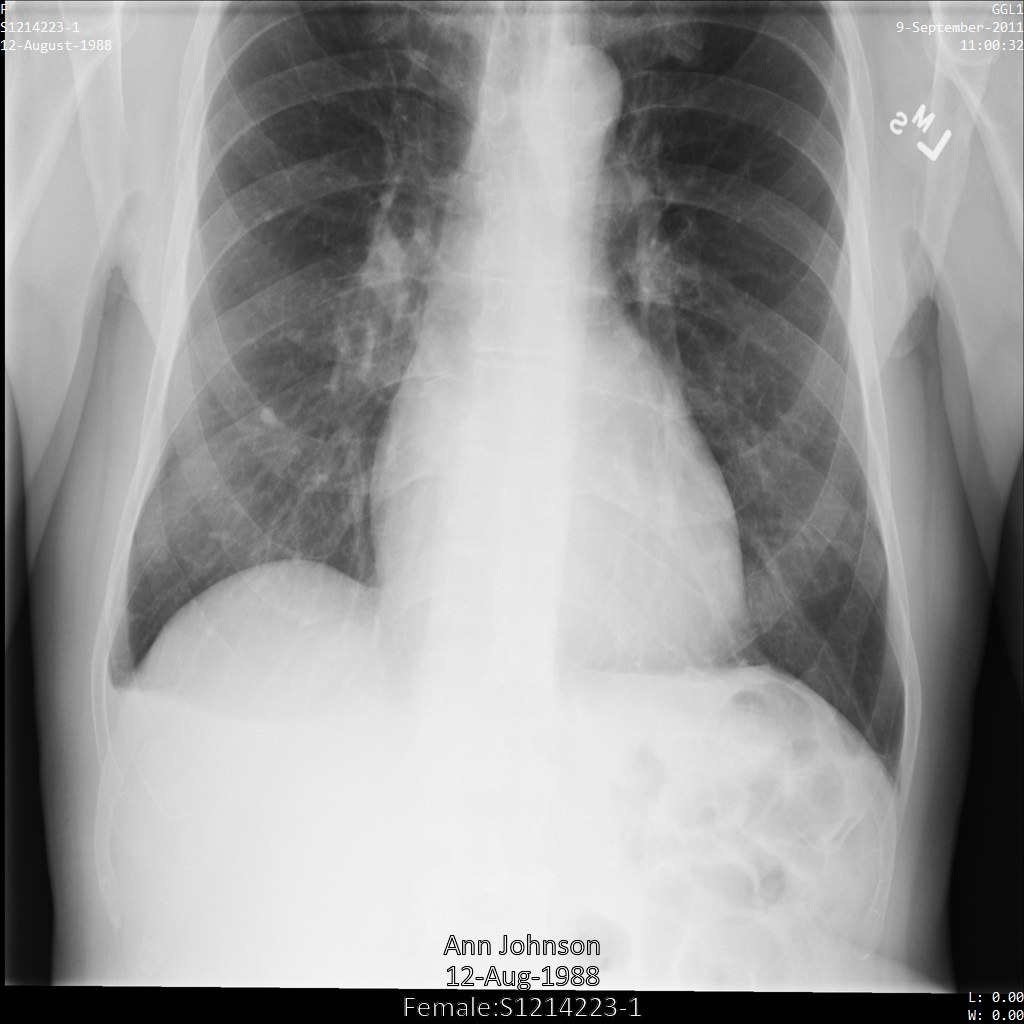

Ciascuna delle sezioni seguenti fornisce esempi di come anonimizzare i dati DICOM utilizzando vari metodi. Con ogni campione viene fornito un output dell'immagine deidentificata. Ogni campione utilizza la seguente immagine originale come input:

Puoi confrontare l'immagine di output di ogni operazione di deidentificazione con l'immagine originale per vedere gli effetti dell'operazione.

Dopo aver inviato l'immagine all'API Cloud Healthcare utilizzando il profilo DEIDENTIFY_TAG_CONTENTS, l'immagine viene visualizzata come segue.

Osserva le seguenti modifiche:

- I nomi nell'angolo in alto a sinistra e in alto a destra dell'immagine sono stati trasformati

utilizzando un

CryptoHashConfig - Le date nell'angolo in alto a sinistra e in alto a destra dell'immagine sono state trasformate

utilizzando un

DateShiftConfig